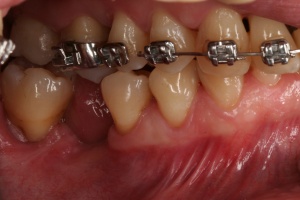

Bevor die Implantatprothetik angefertigt wird, sollten zahnärztlicherseits die periimplantären Weichgewebsverhältnisse erneut geprüft und bewertet werden. Sofern keratinisierte Gingiva periimplantär fehlt, sollte spätestens zu diesem Zeitpunkt ein weichgewebschirurgischer Eingriff (BGT, FST) erfolgen (Abb. 6).

Bevor die Implantatprothetik inseriert wird, überprüft der versorgende Zahnarzt, ob die periimplantären Strukturen sondiert und insbesondere durch den Patienten gepflegt werden können. Dies lässt sich bereits auf dem Meistermodell nach Abnahme der Silikonzahnfleischmaske kontrollieren. Die Krone sollte idealerweise dem Emergenzprofil des Implantates oder des Abutments folgen (Abb. 7a/b).